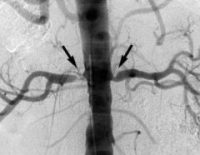

Причины и лечение атеросклероза почечных артерий

Почечный атеросклероз – это заболевание сосудов, снабжающих почки. Атеросклеротическая бляшка, разрастающаяся благодаря соединительной ткани, затвердевает с отложившимися на ней солями кальция и становится препятствием для нормального кровотока. Когда количество крови, поступающей к почкам, уменьшается в результате атеросклероза почечных сосудов, в организме вырабатывается гормон ренин, стимулирующий улучшение кровоснабжения. Давление лишнего объема крови вызывает расширение сосудов, истончение …